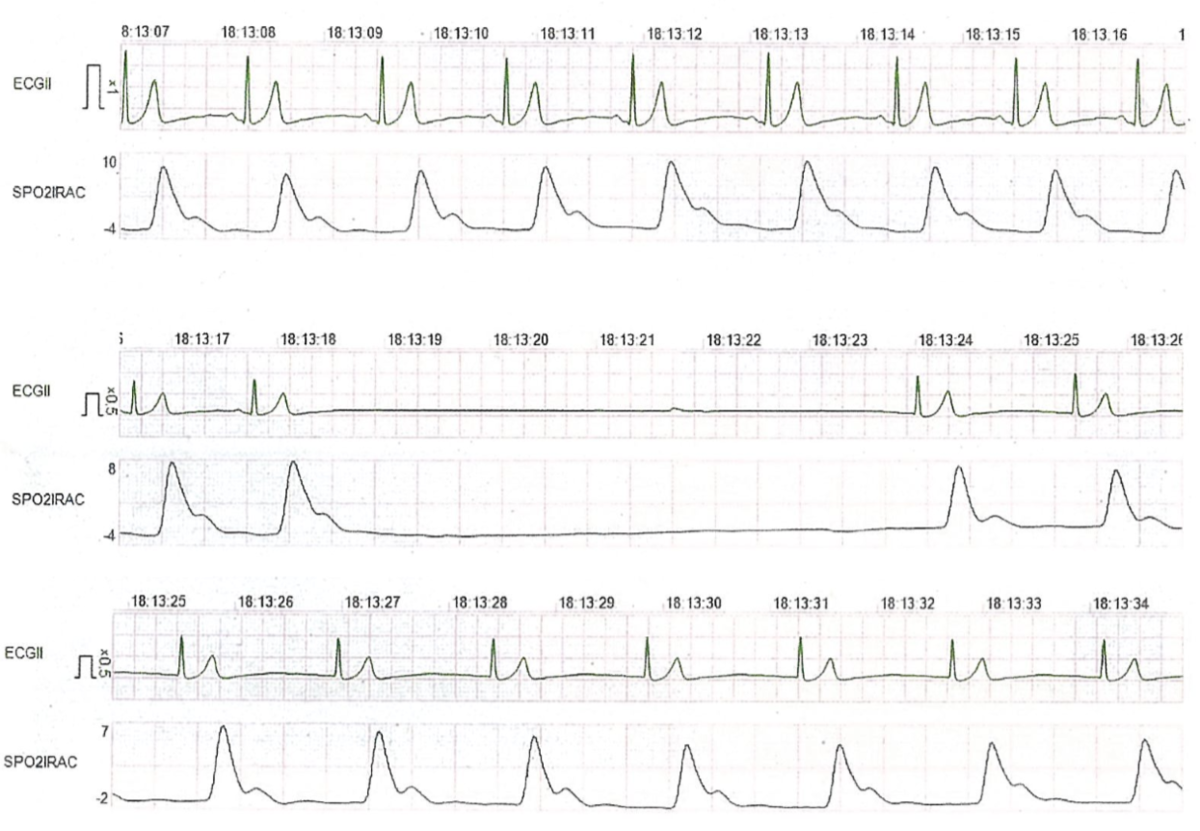

57歳の男性。全身麻酔下に右側の下顎骨嚢胞摘出術を行うこととした。麻酔導入後、気管挿管のために喉頭蓋を持ち上げた時点で心電図の変化を認めた。心電図と脈波の波形を示す。

と予想がついてしまいます。せっかく正常心電図以外の問題が来たのに(笑)。いやいや、まだ断定はできません。視覚素材を見てみましょう。見慣れていないと分かりづらいかも知れませんが、時系列で上中下の3段に分かれています。

こういう感じです。1段目は喉頭展開する前、2段目は喉頭展開したところ、3段目は心電図異常を見て喉頭展開を止めたところ、と考えたら分かりやすいでしょうか。2段目のフラットになっている部分以外は正常に見えますね。心電図も脈波も正常だったけれど(1段目)喉頭展開をしたら心電図も脈波も消失(2段目)、喉頭展開を止めたらすぐ正常に戻った(3段目)、と言う流れとイメージすれば分かりやすそうです。

正解はdの迷走神経反射です。

喉頭展開など喉頭やその他頚部に強い機械的刺激が加わった時、迷走神経咽頭枝や上腕咽頭神経内枝などの迷走神経求心路を介して迷走神経反射を起こす可能性があります。強い徐脈や血圧低下、場合によっては心停止まで。このケースでは幸い一過性で、原因となった刺激の除去によってすぐ回復したということでしょう。